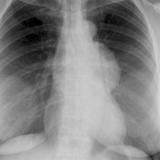

Case 9 Thymoma PA

Date: 04/04/2010

Views: 3171